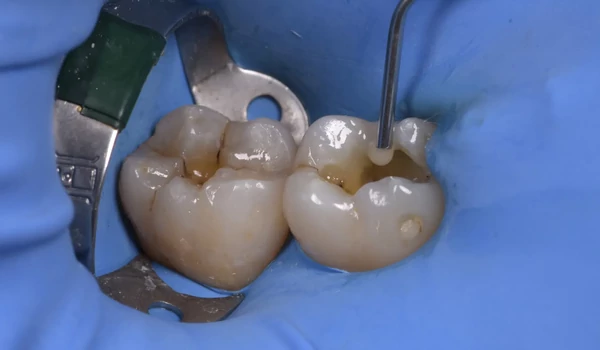

Preparálás 2–3. ábra: amalgám eltávolítása és szuvas részek kitisztítása Az amalgámtöméseket eltávolítottuk, majd a szuvas dentint kitisztítottuk, a lehető legtöbb ép foganyagot megőrizve.

2. ábra A meglévő amalgámtömések eltávolítása utáni állapot. |

3. ábra Tipikus amalgámfestődés látható a nagyobb üreg alján. |

4. ábra Tömési eljárás: A folyékony kompozit első rétegének felvitele. |

5. ábra A második őrlőfog már tömve van, az elsőre egy újabb réteg folyékony kompozitra van szükség. |

6. ábra A feltöltés befejeződött. |